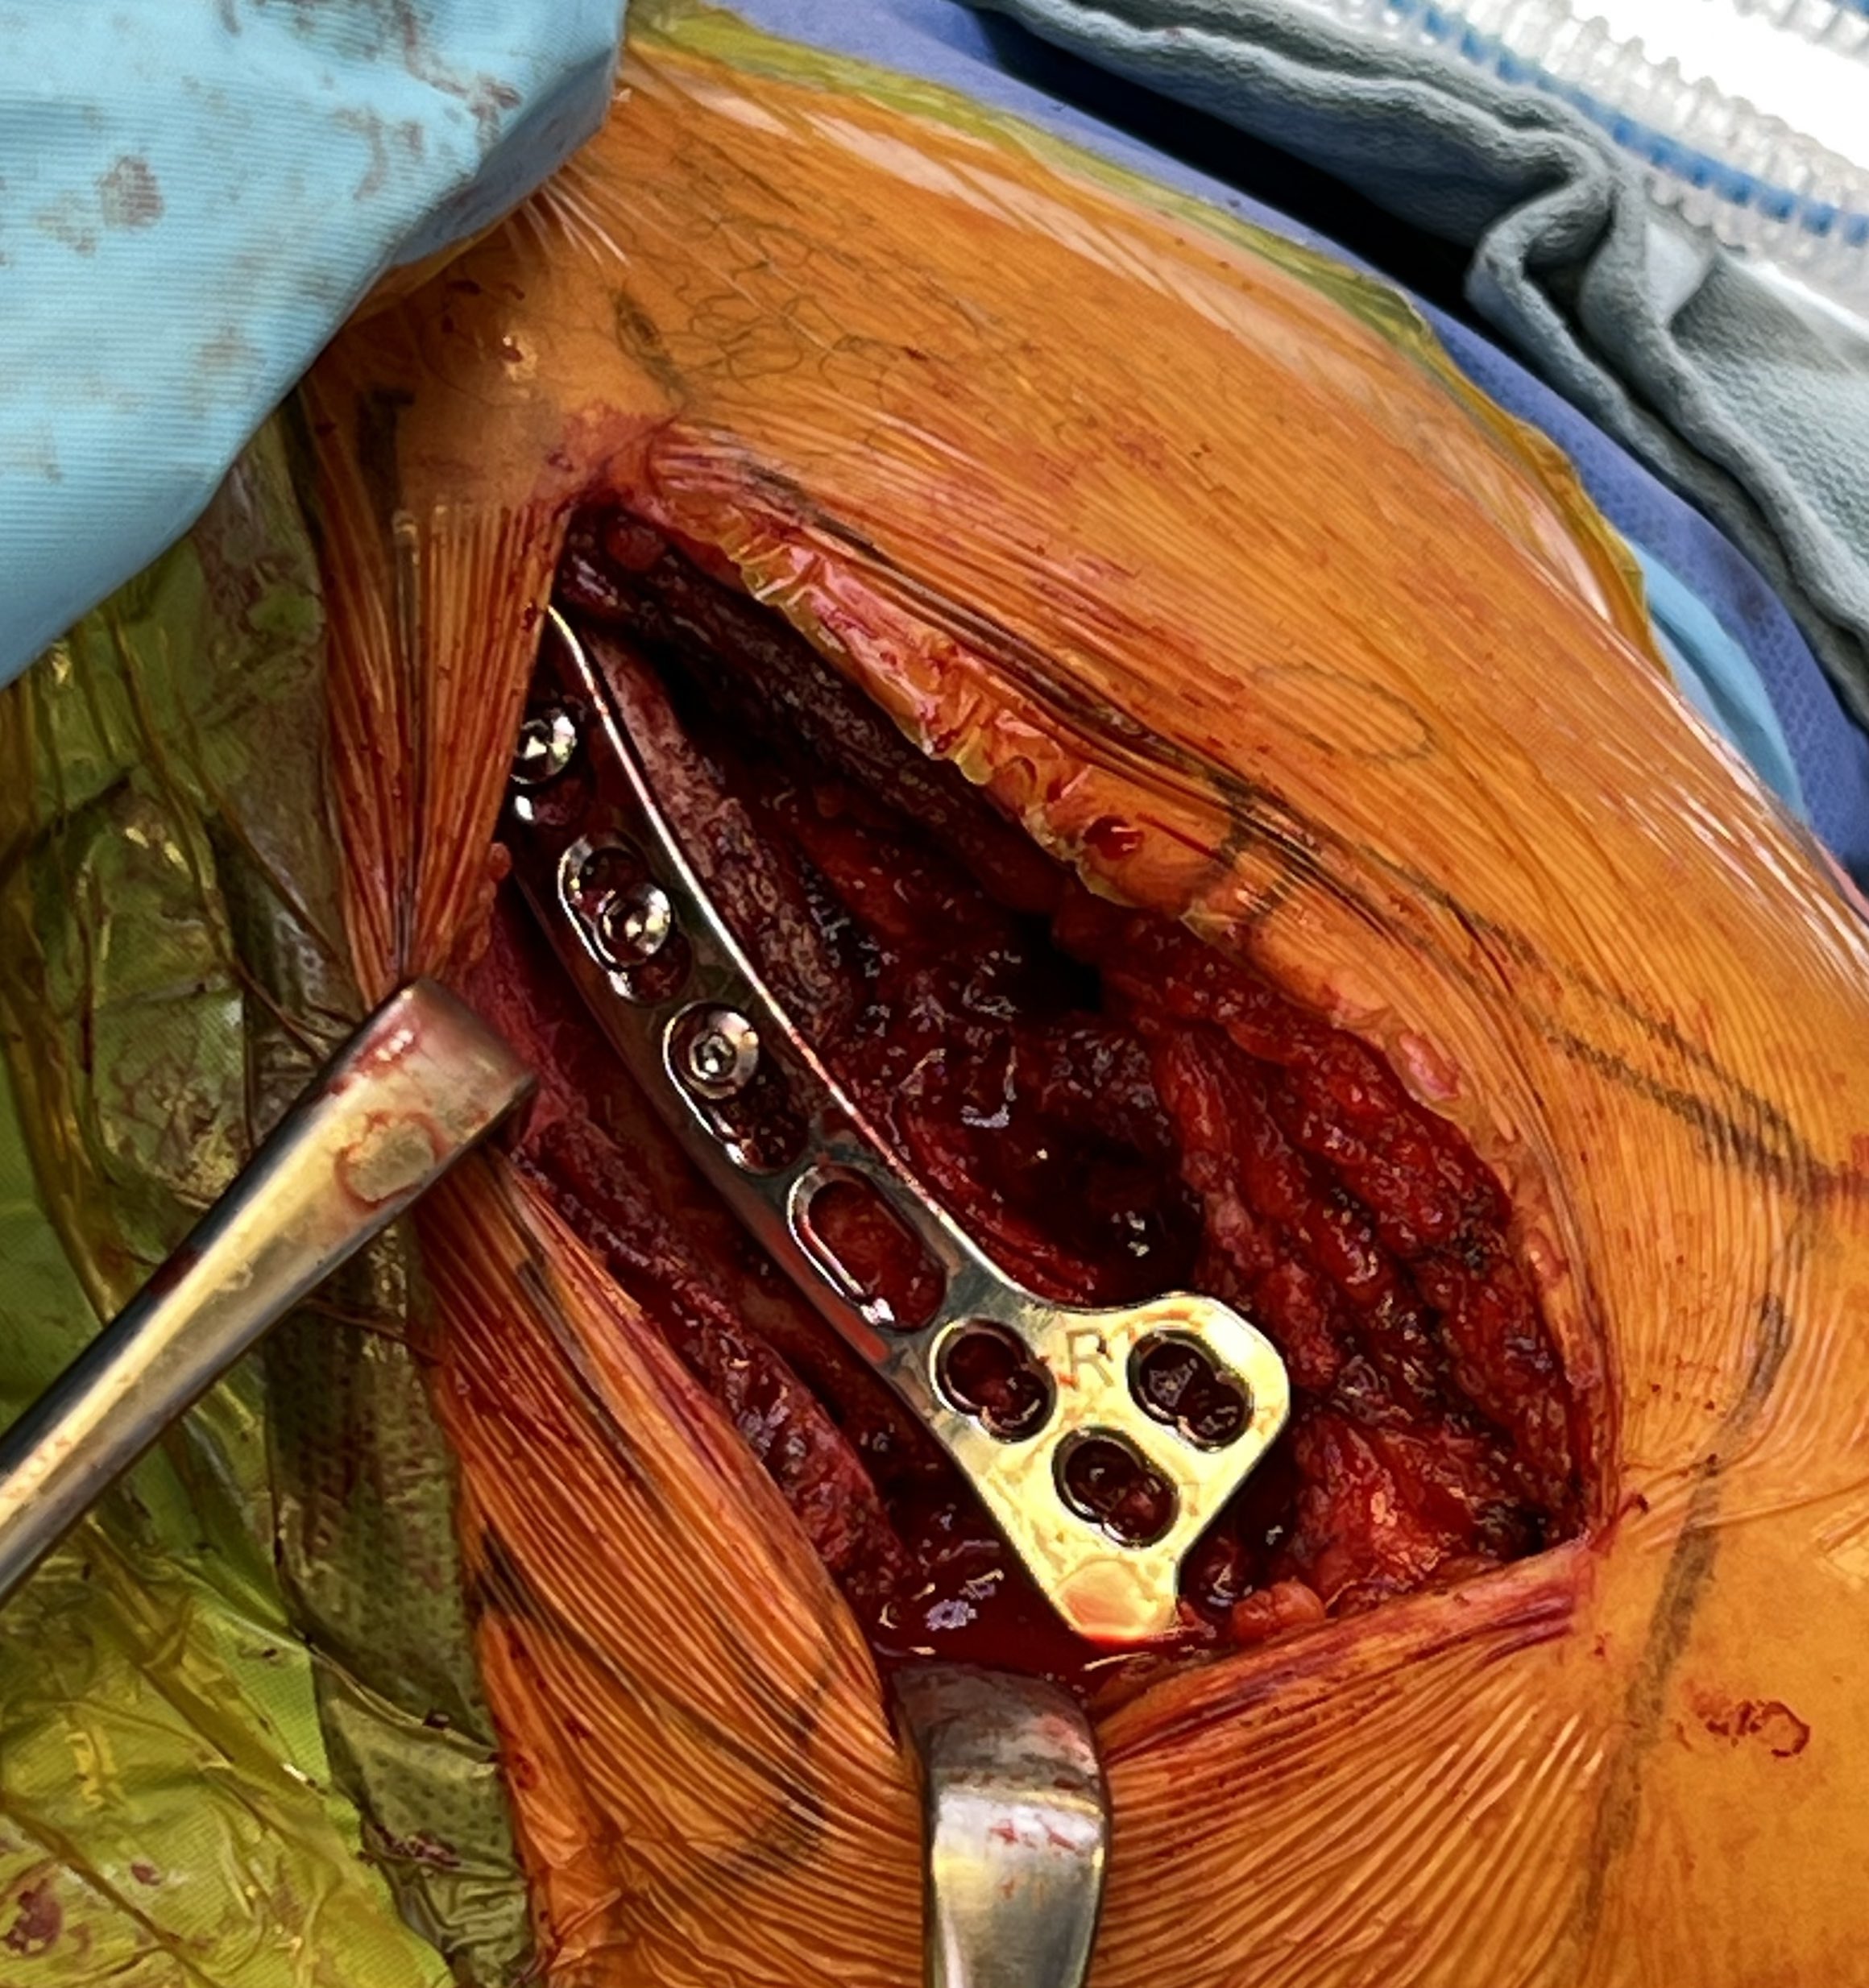

2. Weaver Dunn Reconstruction

Concept

Reconstruction of CC ligament with coraco-acromial ligament (CAL)

Technique

- 45o beach chair

- sabre incision over ACJ

- split deltoid fascia transversely along the clavicle and onto acromion

- expose distal end of clavicle and resect small amount with microsagittal saw

- expose anterior aspect of acromion but identify and preserve CA ligament

- take off anterior 5mm of acromion with CA ligament attached

- carefully peel CAL off the underlying subscapularis

- CA ligament left attached to coracoid

- transferred from acromion to clavicle end

- intra-osseous suture repair through clavicle drill holes

- consider supplement fixation with hook plate / suspensory fixation